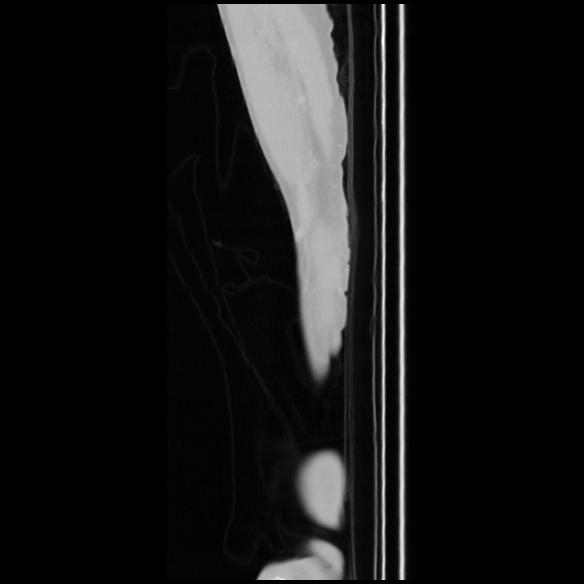

7 CUERPO,CE,Sagittal,3.000,CUERPO,Sagittal,